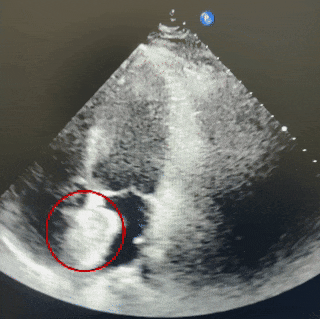

超声四腔心切面下可见封堵器双盘骑跨在房间隔两侧

四腔心切面

封堵器锁定成型后,超声下多切面确认封堵器盘面贴合,稳定夹持缺损。